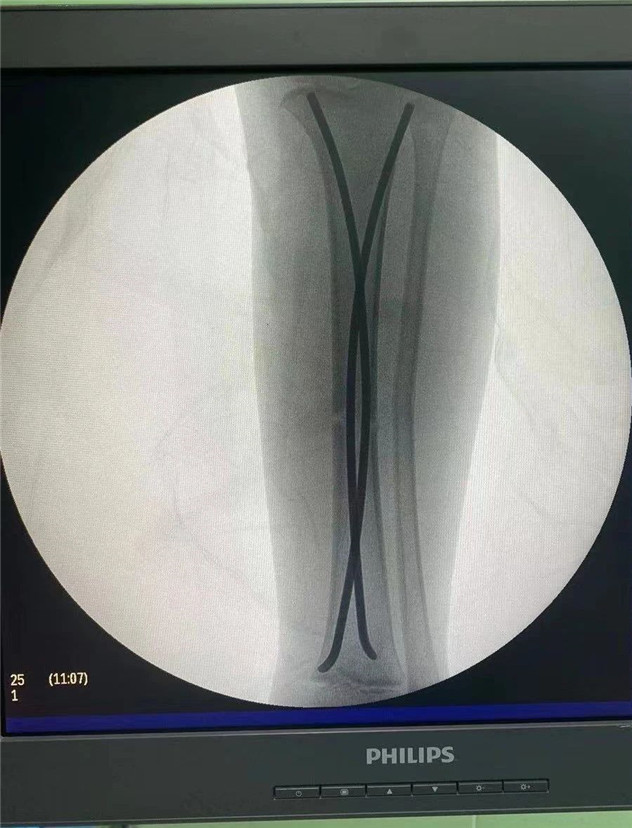

術(shù)中

2020年10月5日,在完成術(shù)前檢查后,睿睿接受了閉合復(fù)位彈性釘內(nèi)固定術(shù),手術(shù)由羅軍主任主刀。術(shù)中只需要兩個(gè)1厘米的小切口,精準(zhǔn)微創(chuàng),僅一個(gè)小時(shí),手術(shù)便圓滿完成。

據(jù)羅主任介紹,兒童骨折絕不是成人骨折的縮小版。兒童的不穩(wěn)定性脛骨骨折或雙側(cè)脛骨骨折,保守治療很難達(dá)到理想復(fù)位,可能會(huì)造成肢體不等長、成角旋轉(zhuǎn)畸形、肌肉萎縮等并發(fā)癥。而彈性髓內(nèi)釘?shù)膽?yīng)用,正好解決了患者和醫(yī)生所擔(dān)心的問題,既理想地固定了骨折,又不影響肢體美觀,可謂一舉兩得。“彈性髓內(nèi)釘”技術(shù)可在保護(hù)骺板不受損傷的前提下,利用多點(diǎn)固定的原理,微創(chuàng)、有效地治療3—15歲的四肢長骨骨折患兒。手術(shù)在C型臂全程引導(dǎo)下,只需在骨折遠(yuǎn)、近端各切一2—3cm切口打入彈性髓內(nèi)釘,創(chuàng)傷極小,不影響孩子的骨骼發(fā)育,對(duì)于骨折的愈合以及孩子以后骨骼發(fā)育影響小。相比之下,既有效避免了切開復(fù)位鋼板內(nèi)固定創(chuàng)傷大、疤痕大等缺點(diǎn),又有效避免了支架外固定鋼針外露、不易護(hù)理等弊端。